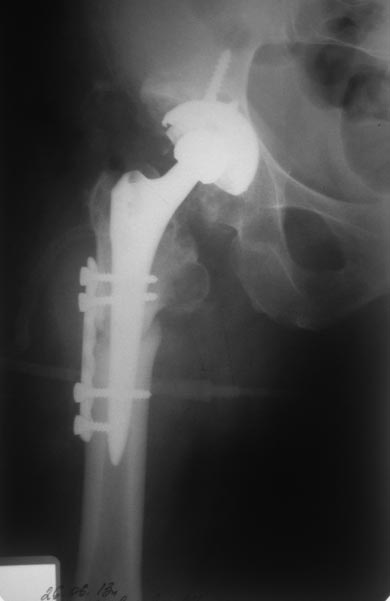

Здравствуйте, коллеги! Планируется эндопротезирование суставов у пациентки с врожденной аномалией развития скелета Пациентка 48 лет, врожденная аномалия скелета. В настоящее время поступила с диагнозом:Диспластический коксартроз III ст справа, вывих левого бедра (Crowe IV). Гонартроз слева III. Варусные деформации обоих бедер. Сгибательная, приводящая, ротационная контрактура правого тазобедренного сустава. Сгибательная контрактура левого коленного сустава. Из анамнеза: Больна с детства, в возрасте 15-17 лет субспинальные миотомии с обеих сторон, отсечение большого вертела слева дополненное скелетным вытяжением.Планируется: Первым этапом эндпротезирование правого тазобедренного сустава с одномоментной коррекцией варусной деформации. Вторым этапом эндопротезирование слева с укорачивающая и корригирующей остеотомией. Третий - левый коленный сустав. У кого есть опыт протезирования подобных пациентов, прокоментируйте пожалуйста. Может что недооцениваем.

На днях прооперировали. Основная проблема была при обработке проксимльного фрагмента поле остеотомии. Были сложности с адаптацией фрагментов но контакт достаточный, стабильность хорошая, надеюсь что проблем со сращением не будет